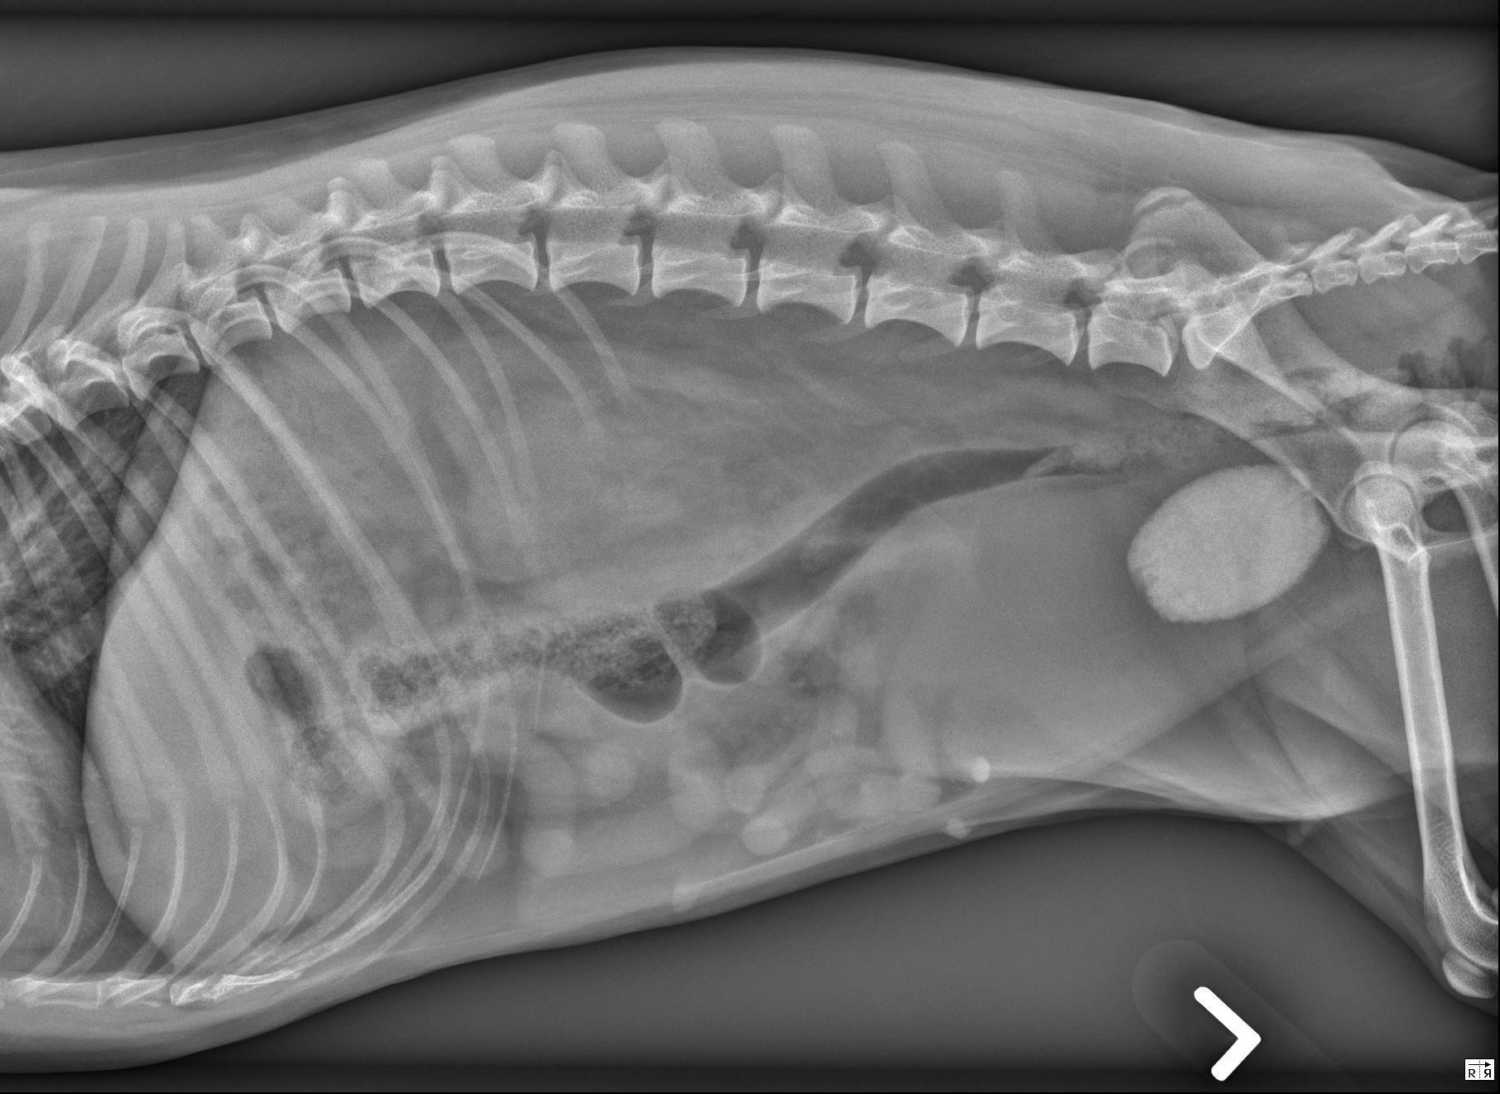

Radiologie Quiz Oktober 2025

In samenwerking met Dr Adrien-Maxence Hespel van de Universiteit van Tenessee bieden we volgende radiologie quiz aan. Het doel van deze casus is om te…